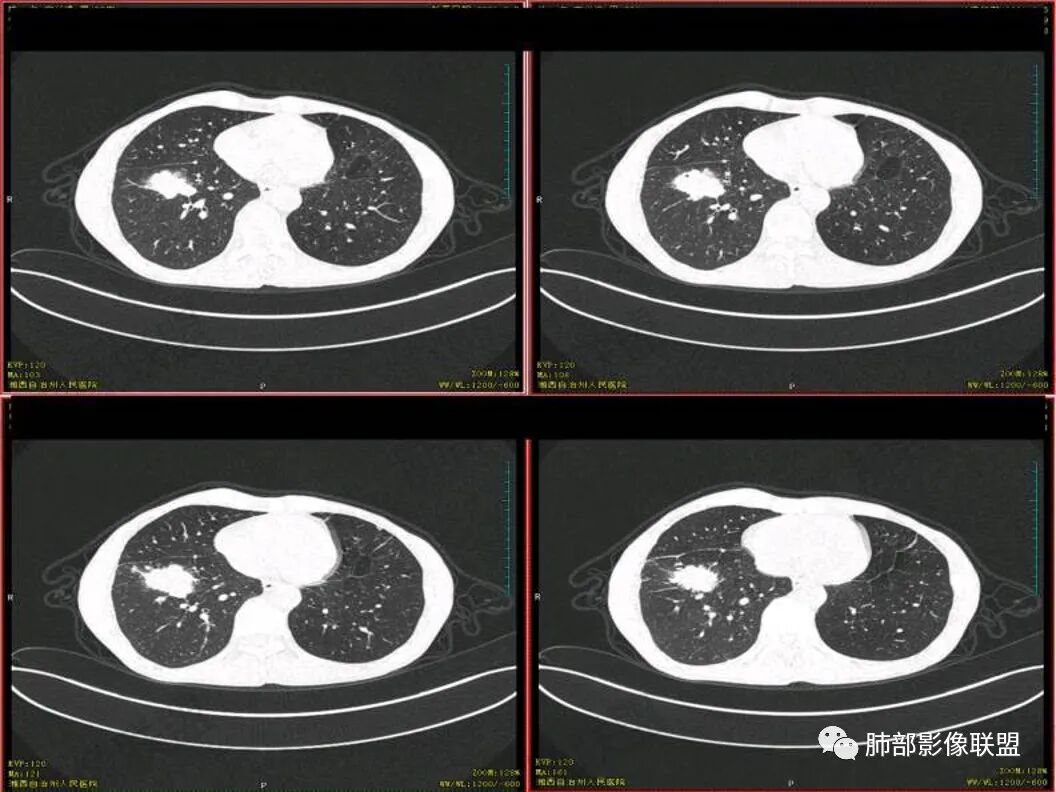

老年男性,既往有肺结核病史。影像双上肺病灶考虑陈旧性肺结核病灶,关键是右下肺团块影,从视频看,右下叶前段分支有堵塞,病灶局部膨隆,有分叶,周围有磨玻璃,但边界不大清楚,远端还有可以阻塞性炎征象,内部有偏远心端坏死,故考虑恶性可能性大。

结核,一般规律治疗的复发概率比较低,所以没有把右下肺的病灶优先考虑为结核

结核和肺癌鉴别,因为淋巴结坏死疾病就这两种,坏死来看并不像小细胞肺癌。主病灶膨隆,增强后,壁厚薄不均,有壁结节感觉,首先是不能放弃的是肺癌这个诊断。具体哪一种还是主要看病理,建议支气管镜穿刺淋巴结的。

影像表现为 双肺上叶多发索条斑片影,可见支气管牵拉性扩张,考虑为陈旧肺结核纤维硬结灶。右肺下叶前基底段团块影膨隆生长,边界不清,呈分叶,毛刺,胸膜牵拉,支气管截断,中央区坏死明显,但未形成空洞,坏死区边缘光整,不均匀环形强化,隐约见壁结节。纵隔淋巴结肿大伴钙化,病灶远端见阻塞性炎症,结合CYFRA21-1偏高,应想到考虑恶性病变,鳞癌可能性大。